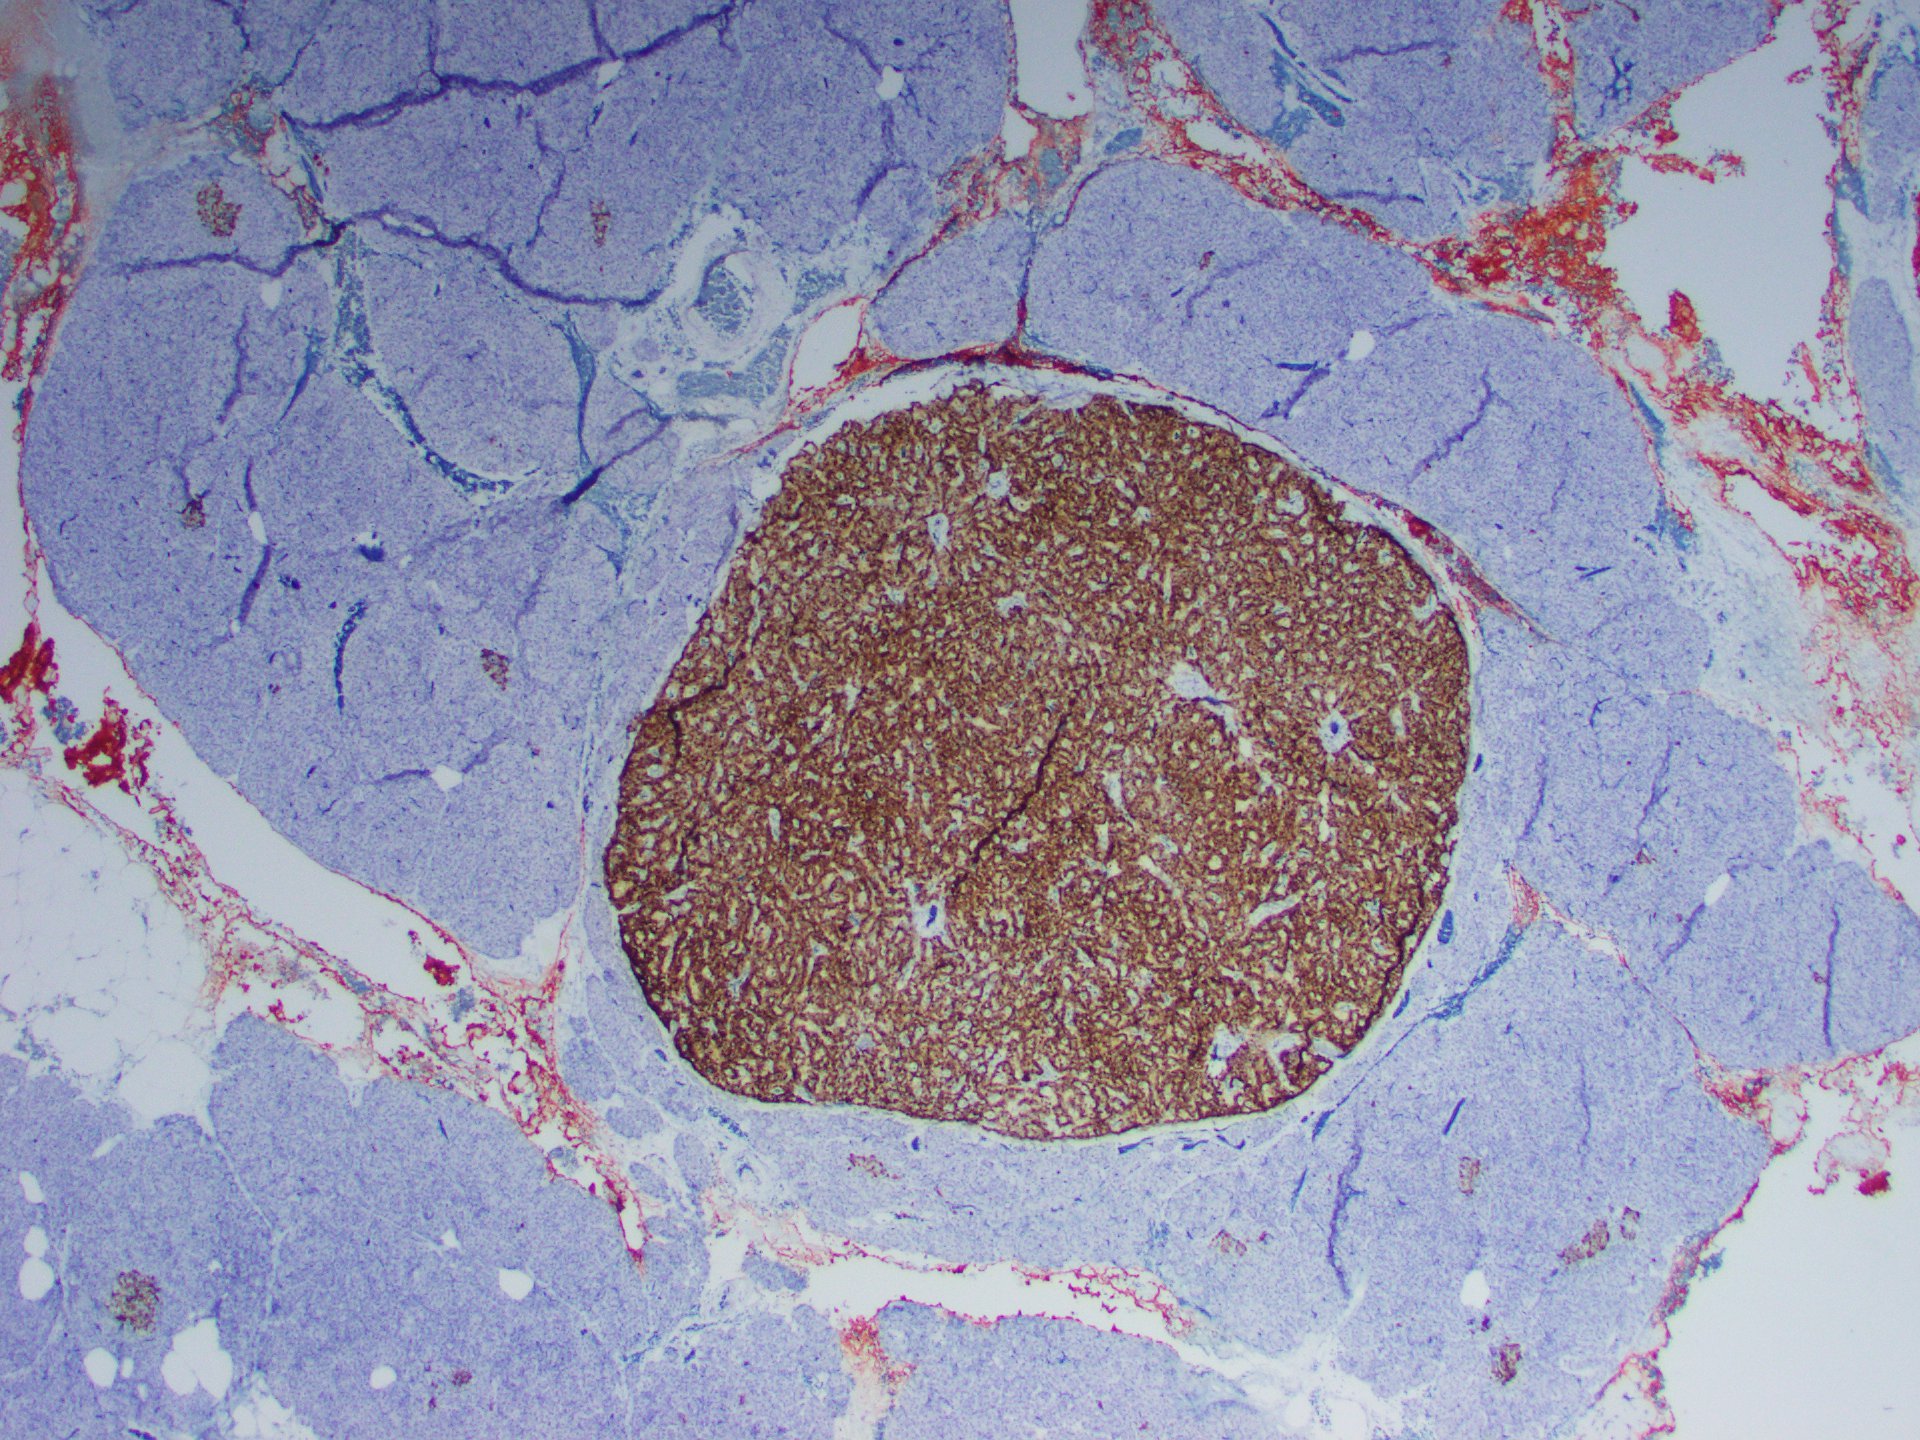

Abdominal CT showed a hypodense lesion in the tail of the pancreas. A follow-up MRI confirmed a 2.4 cm pancreatic mass and incidental bilateral non-obstructing renal calculi. Distal pancreatectomy was performed.

Gross examination of the distal pancreatectomy and splenectomy specimen revealed a 2.6 cm firm, well-circumscribed, homogeneous, yellow/tan intrapancreatic tumor and an unremarkable spleen.

On microscopy, the tumor consisted of a monotonous population of round cells with dispersed fine chromatin, prominent central nucleoli, and a moderate amount of cytoplasm (Figures 1-5). Also, multiple small neuroendocrine lesions of similar appearance (microadenomas; Figures 6-9) were seen.